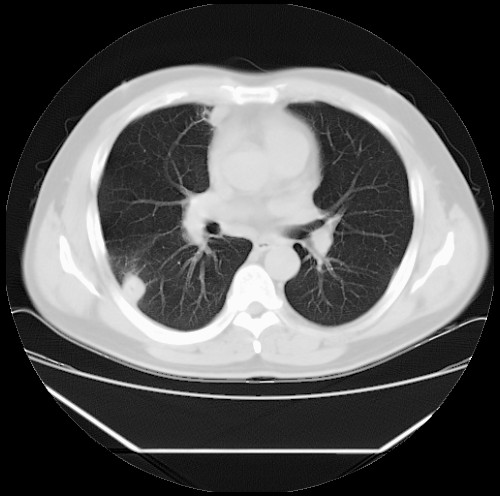

标题: CT22085:双肺多发结节

男,44岁,咳嗽,痰中带血2天。

病灶大部分位于胸膜下,结节大小相差不是很大,肺尖太干净。这种结核没见过,我认为可排除。

除肺内及胸膜下可见多发大结节外,在肺小叶中心核、小叶间隔及支气管血管束上亦可见多方小结节,可以认为是随机分布。考虑转移可能性大。

仔细观察病灶形态,病灶边界部分清楚,结合临床症状,首先考虑转移,纵隔内多个肿大淋巴结影。

双肺血管纹理末端多发类圆形结节,边界光滑清晰 气管前腔静脉后淋巴结肿大

考虑转移瘤

沿血管分布,位于血管末端。转移瘤多见,血行性菌栓也可见到。

本例双肺多发类圆形高密度灶,边清,结合病史多考虑双肺多发转移改变,可以结合实验室检查。